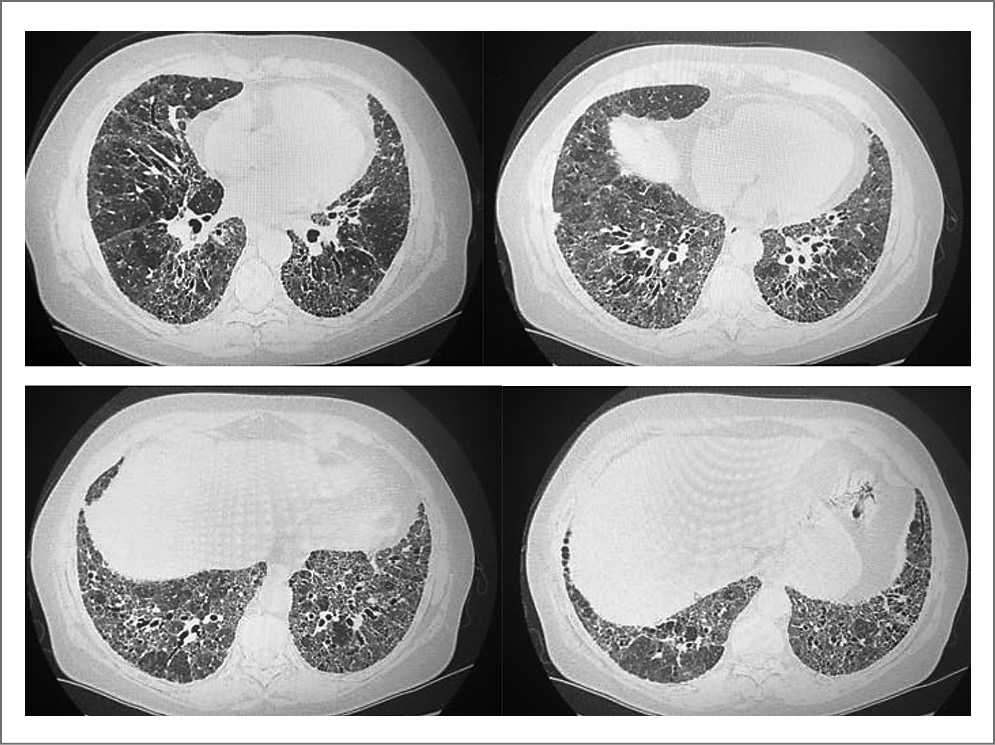

По данным ВРКТ органов грудной клетки также отмечается стабилизация процесса (рис. 2).

Рис. 2 Компьютерные томограммы органов грудной клетки пациентки П., 2021 г.